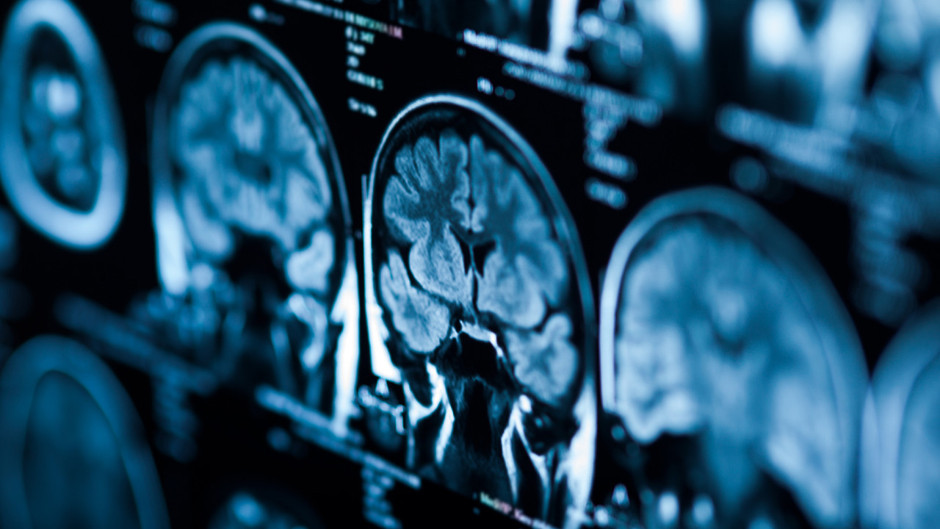

Sesler bu kez çok daha somut bir adım atarak kadına Londra’daki büyük bir hastanenin tam adresini verdi. Zihnindeki seslerin geçmişine dair bazı detayları doğru bildiğini fark eden kadın, onlara güvenmeye başladı. Verilen adrese gittiğinde karşısında bir hastanenin tomografi bölümünü buldu. Sesler içeri girmesini, beyninde hem bir tümör hem de iltihaplanma olduğunu söylüyordu. Hastanın yaşadığı büyük panik üzerine Doktor Azuonye, onu rahatlatmak amacıyla bir beyin taraması istedi.

Başlarda gereksiz görülen bu talep kabul edilince, ortaya çıkan sonuç tıp ekibini şoka uğrattı. Tarama sonuçları, kadının beyninde "menenjiyom" adı verilen oldukça büyük bir tümörün varlığını onayladı. İlginç olan ise hastanın ne şiddetli bir baş ağrısı ne de görme bozukluğu gibi bu boyuttaki bir kütleden beklenen klinik belirtileri göstermemesiydi. Başarılı bir ameliyatla tümör alındıktan sonra, kadın o sesleri son bir kez daha duydu: "Sana yardım edebildiğimiz için mutluyuz. Hoşça kal."